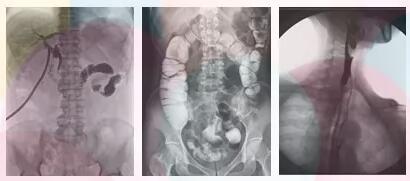

普愛醫(yī)療的動(dòng)態(tài)平板dr的PLD9000A拍攝效果

方面二、胃腸道檢查,優(yōu)選動(dòng)態(tài)平板dr

在胃腸檢查過程中即可獲得流暢的動(dòng)態(tài)影像,又可獲得高清晰的靜態(tài)影像,完整的將患者影像進(jìn)行數(shù)字化存儲(chǔ) ,便于后期的復(fù)查和對(duì)比。

方面三、子宮輸卵管造影,優(yōu)選動(dòng)態(tài)平板dr

采集面積大,一次曝光即可顯示整個(gè)盆腔,大幅減少觀察時(shí)間,可控的瞬時(shí)照射避免受檢者吸收過多的X線,對(duì)育齡期婦女的檢查尤為重要。實(shí)時(shí)高清點(diǎn)片,可以在造影劑流動(dòng)的過程中完成拍片,抓拍到關(guān)鍵圖像,清楚的了解管腔的具體通暢情況及堵塞部位,對(duì)檢查及診斷有非常重要的價(jià)值。